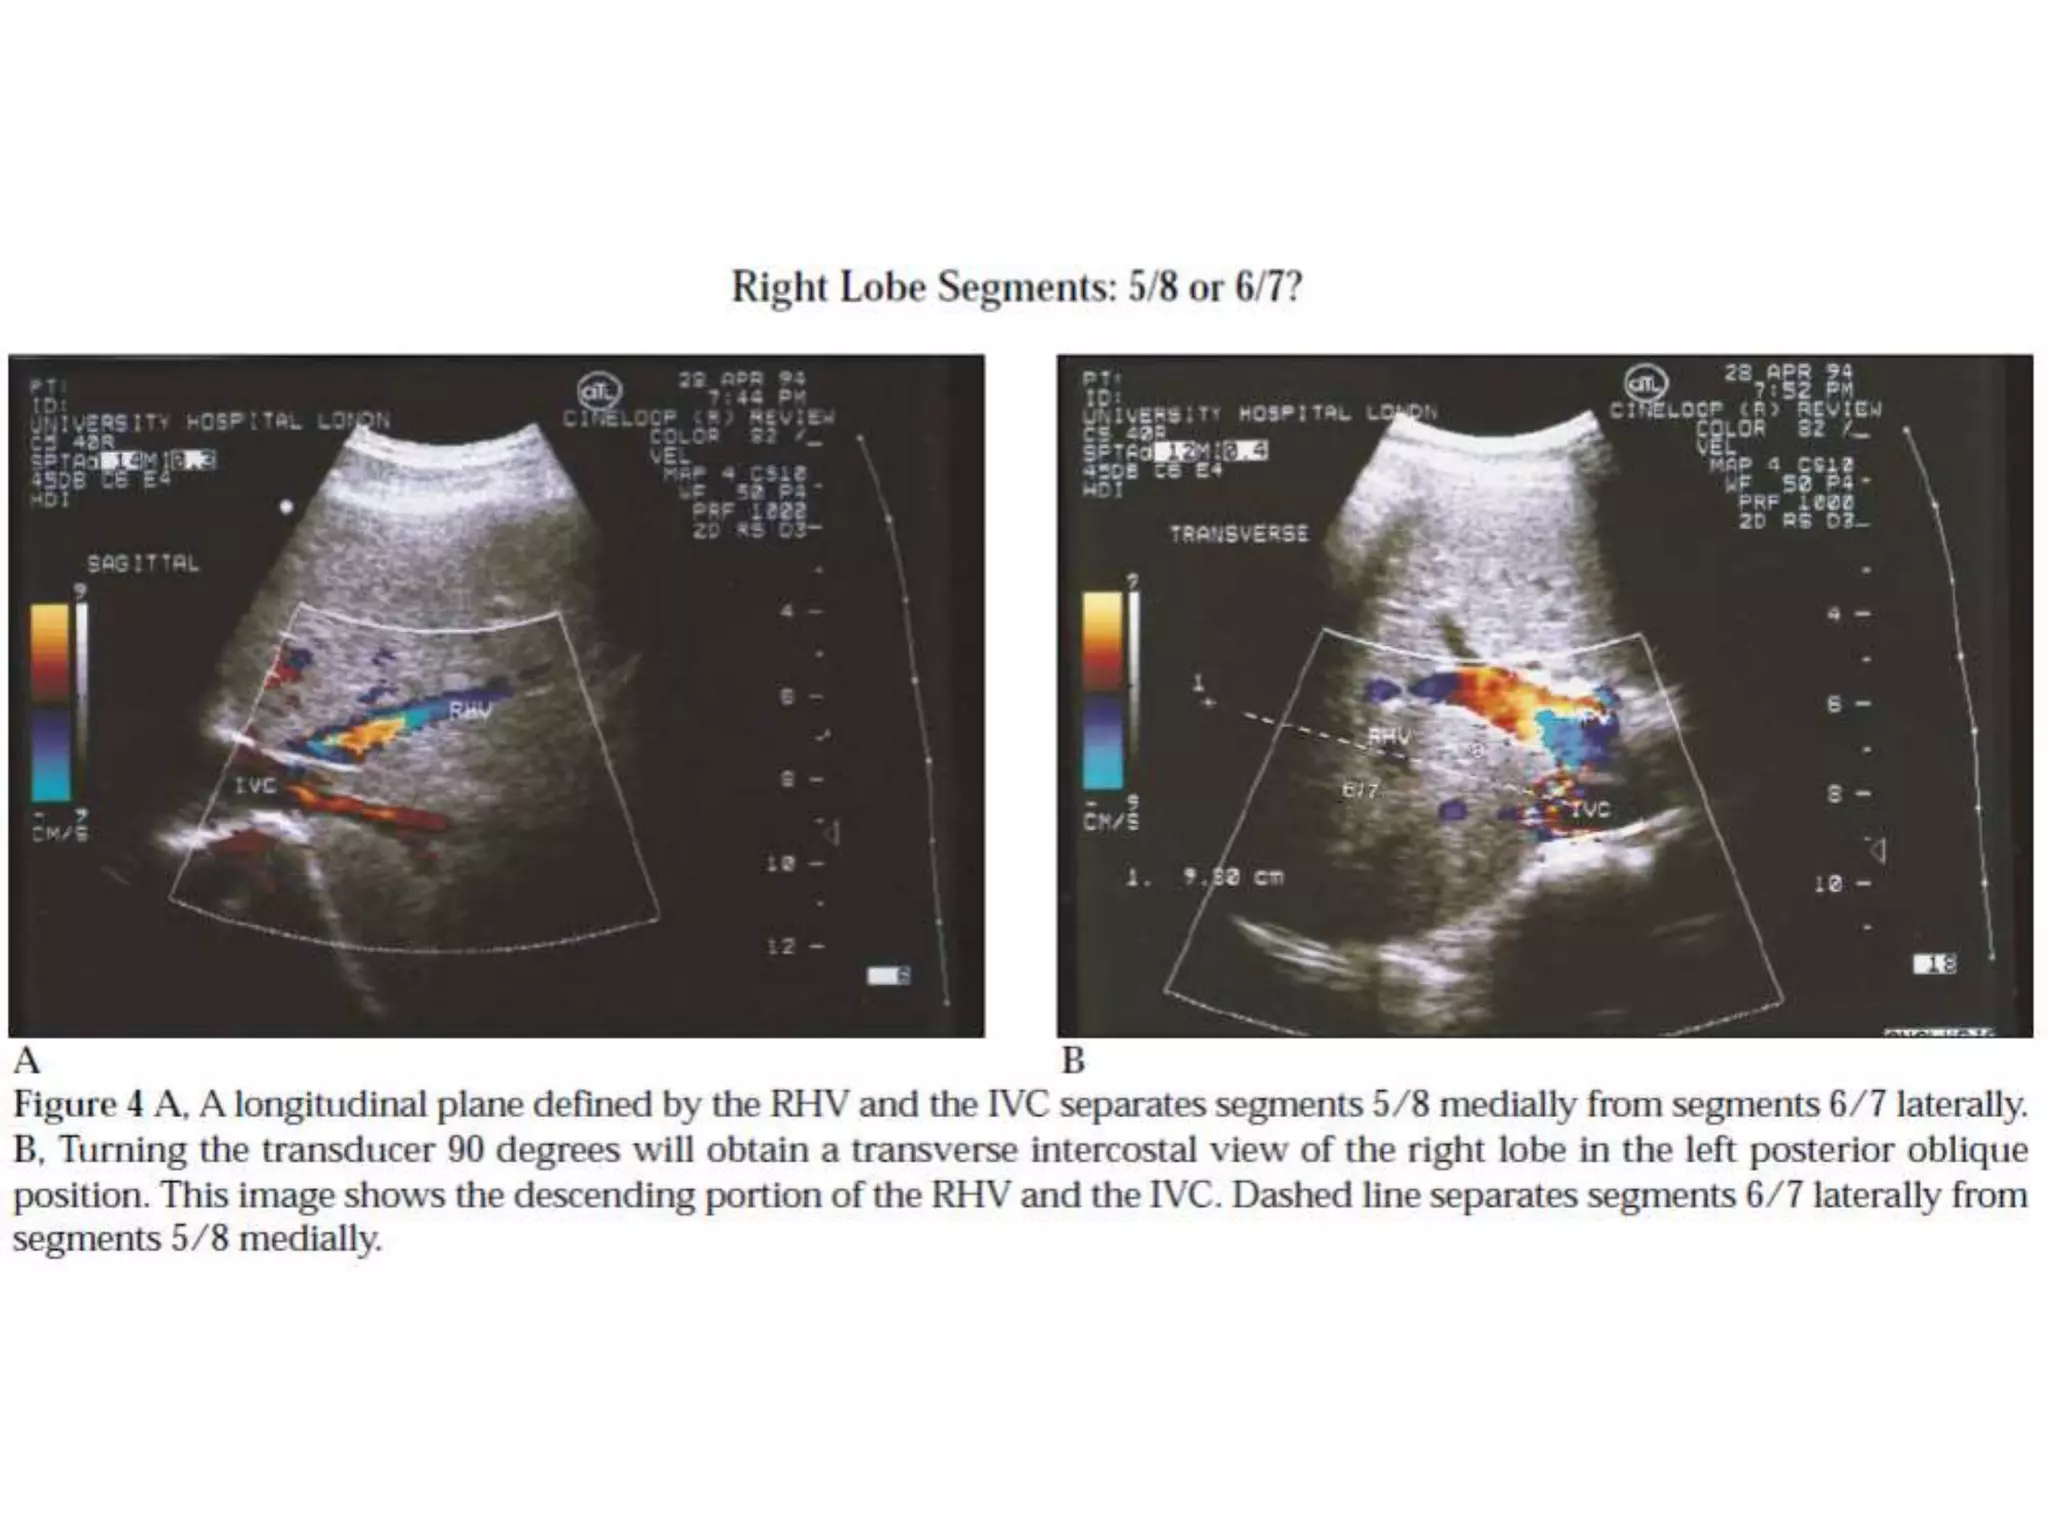

How to separate liver segments

on cross sectional imaging

Right lobe: anterior (V/VIII) vs

posterior segment (VI/VII)

Extrapolate a line along the right

hepatic vein from the IVC inferiorly to

the lateral liver margin (green line).